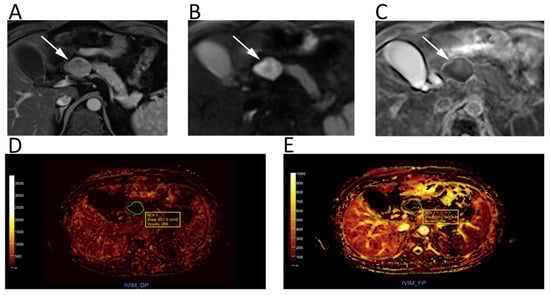

6. Hepatobiliary

| Hepatobiliary | Miller, F.H.; et al. J. Magn. Reson. Imaging 2010 [32] | Retrospective; 542 focal liver lesions in 382 patients; 1.5T MRI. | Mean ADC (10−3 mm2/s) of hemangiomas = 2.26, FNH = 1.79, adenomas = 1.49, abscesses = 1.97, HCC = 1.53, and metastases = 1.50. Mean ADC of benign lesions = 2.50, malignant lesions = 1.52. Overlap reported between solid benign and malignant lesions. |